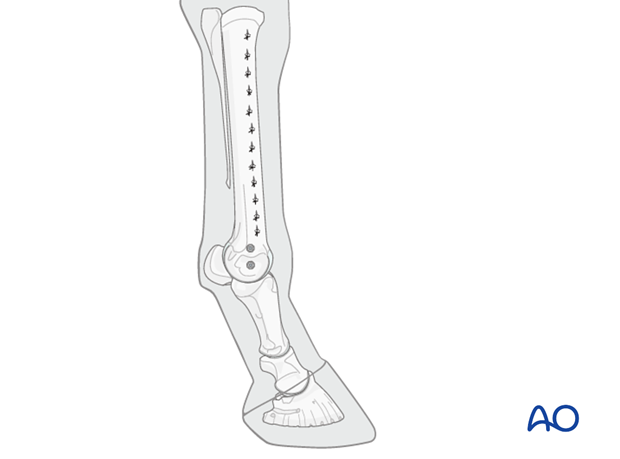

A plate of appropriate dimensions is selected. In metacarpal fractures, a 10-11 hole broad 4.5 mm plate is usually used and in metatarsal fractures, a 12-13 hole plate is used in an average sized race horse. Although, traditional plates can be used successfully, locking compression plates (LCPs) are probably superior.

At least one additional cortex screw is placed through the proximal aspect of the plate to pull it down against the bone. Often, about 50% of the holes in the plate are filled with cortex screws, because they are less expensive than locking head screws. It is essential, that all cortex screws be placed and tightened before the first locking head screw is inserted.

4.5 mm cortex screws are easier to place through the plate holes and generally strong enough, but 5.5 mm cortex screws may be used, especially in larger horses.

The remaining screw holes are filled with appropriate length 5.0 mm locking head screws.